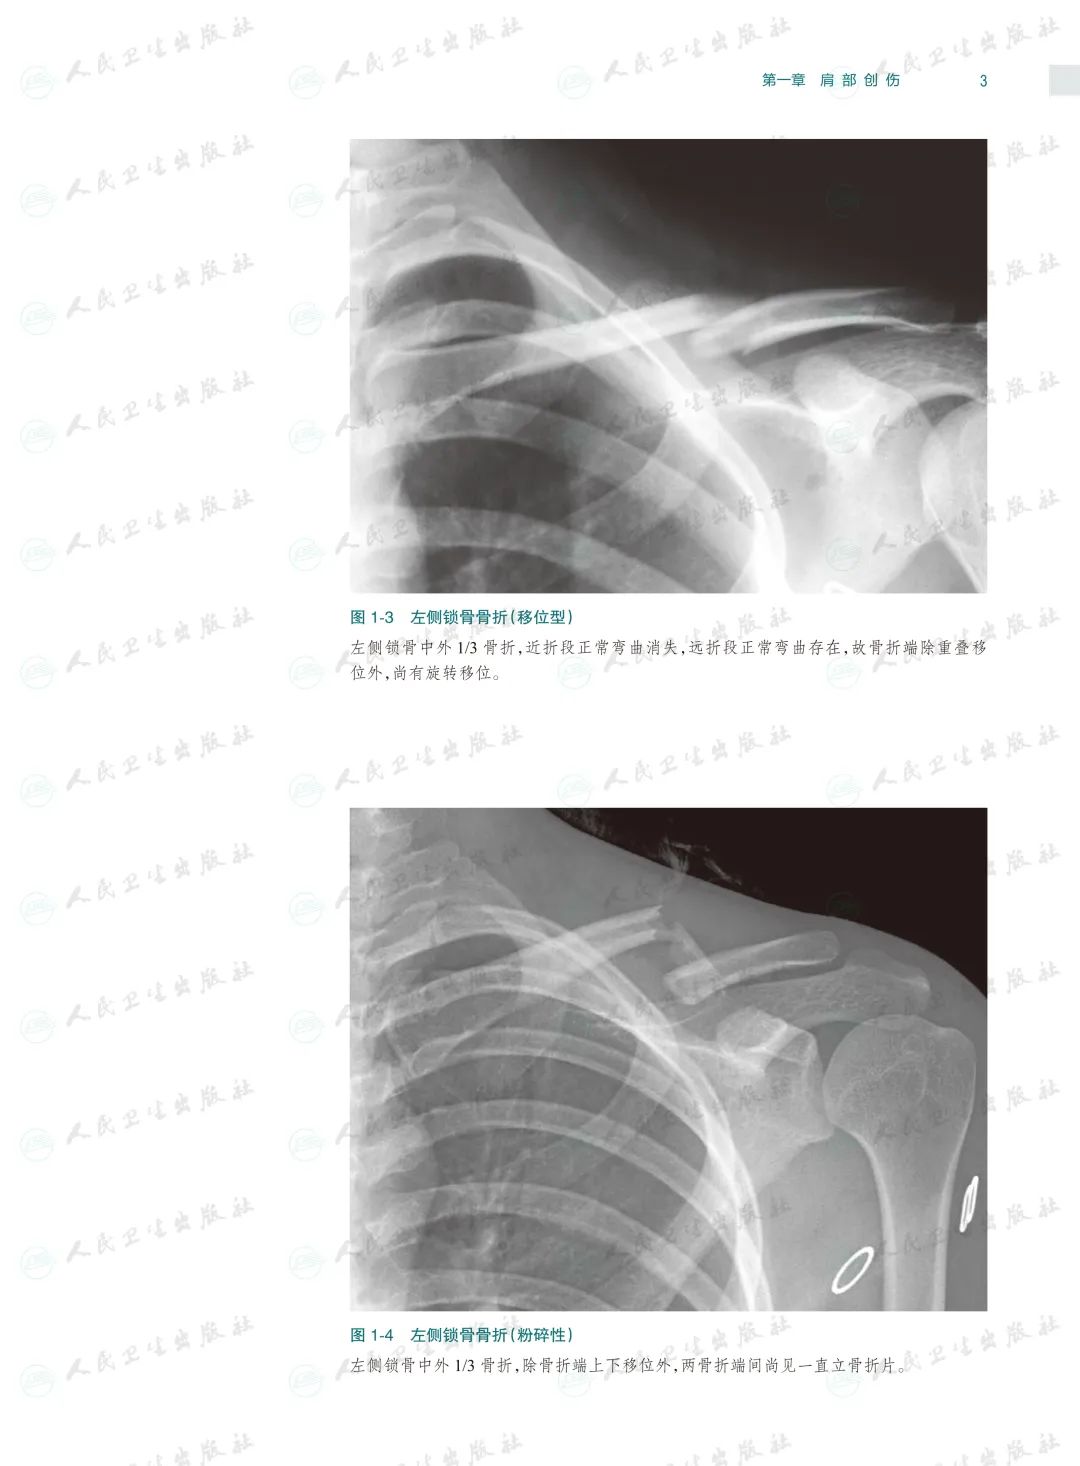

骨关节创伤是骨科临床常见病,X线检查是其最基本和最常用的检查方法。本书以临床典型病例X线检查资料为素材编写,已是第4版了,一直以来本书都因为其实用性而深受读者的喜爱,本次修订根据近几年骨关节创伤领域的#新进展,对目录进行了重新编排、对过时内容进行了修改、对清晰度和对比度欠佳的图片进行了替换,同时还充实了10多个病种的病例图片,并新增了常见骨关节创伤后遗症及并发症章节。

本书以图片展示为主,内容丰富,几乎包括了除头面部以外各个部位的骨关节创伤类型,图片清晰且有详细文字注解,每一章节的创伤类型、诊断要点和鉴别诊断均作了简要叙述。由于图片都是来自作者日常工作的资料积累,因此实用性较强,是一本不可多得的参考书。

本书在第3版基础上修订而成,是一本系统全面介绍骨关节创伤X线诊断的图谱专著。全书共十六章,前十五章每章基本按创伤类型、诊断要点和鉴别诊断体例编写,最后一章介绍常见骨关节创伤后遗症及并发症。书中共选用1270幅X线照片图,约760个病例,所选图片和病例均具有代表性,可使读者对各部位、各类型的骨关节创伤及其后遗症和并发症有进一步认识,从而提高诊断水平。本书主要供骨科医生、影像科医生及医学院校相应专业的学生使用。